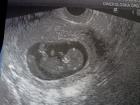

FORUMŠICE MOJE JOJ KOJE LI SREĆE KOD NAS U KUĆI

JUČER JA BEZVEZE KUPIM TEST I NAPRAVIM DA SE UVJERIM DA TREBAM DOBITI JER MI SAMO LAGANO GRČI MATERNICA I DOJKE ME BOLE, A MENGU TREBAM DOBITI 10.06.2012. I POKAŽE MI POZITIVNO.......

ja svom mužu uletim u krevet, a on onako sanjim spavaj ženo jesi ti normalna, kad sam mu tutnula pod nos on je skoro od plafon udario glavom koliko je poskočio od sreće, ali se izgubio jer nije znao jel to OVULACIJA i opet Keks ili šta...

kad sam mu rekla da je to test samo je zaplakao i zagrlio me.....

mi smo jjoš u šoku, u ponedjeljak idem ginekologici svojoj da vidimo malu mrvicu, ako se uopće vidiiiiii